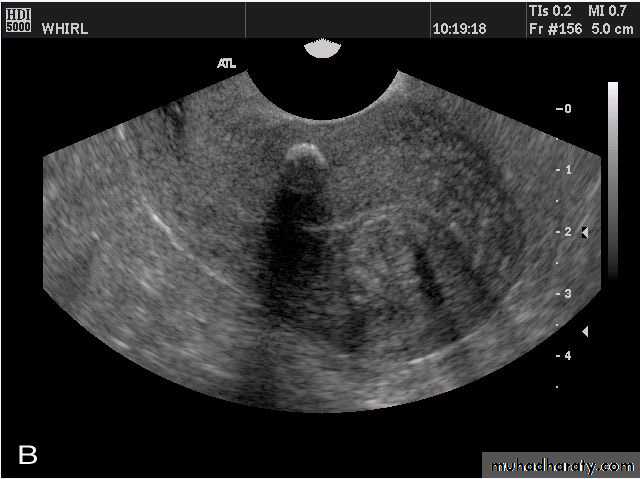

Normal Uterus in longitudinal viewUterine Pathology